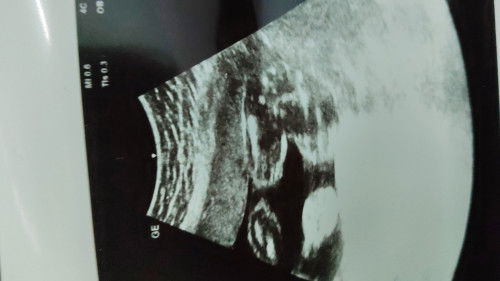

its a boy?

scan 20w, menunjukkan pistol… ad x mommies scan pistol, tp kluar girl.. kita nak kemas2 baju2 girl kakak nya pnya, nk bagi sedara mara.. tp masih dilema lagi, tkot kne scam..

Sayapun siss scan masa 24w nmpak bgini boy kata doktor tapi dilema lah jgk sbb takut kena scam hahaha btw anak pertama girl skrg tunggu hari je beli baju pun unisex ja

yg ini doc siap tunjuk telur.. scan 28w pn kata boy jgk..

ini boy. pnglmn sy 17w dh nmpk boy. repeat 25w boy..lahir pun boy. baju kakak dia byk sy letgo .tinggal yg unisex shj